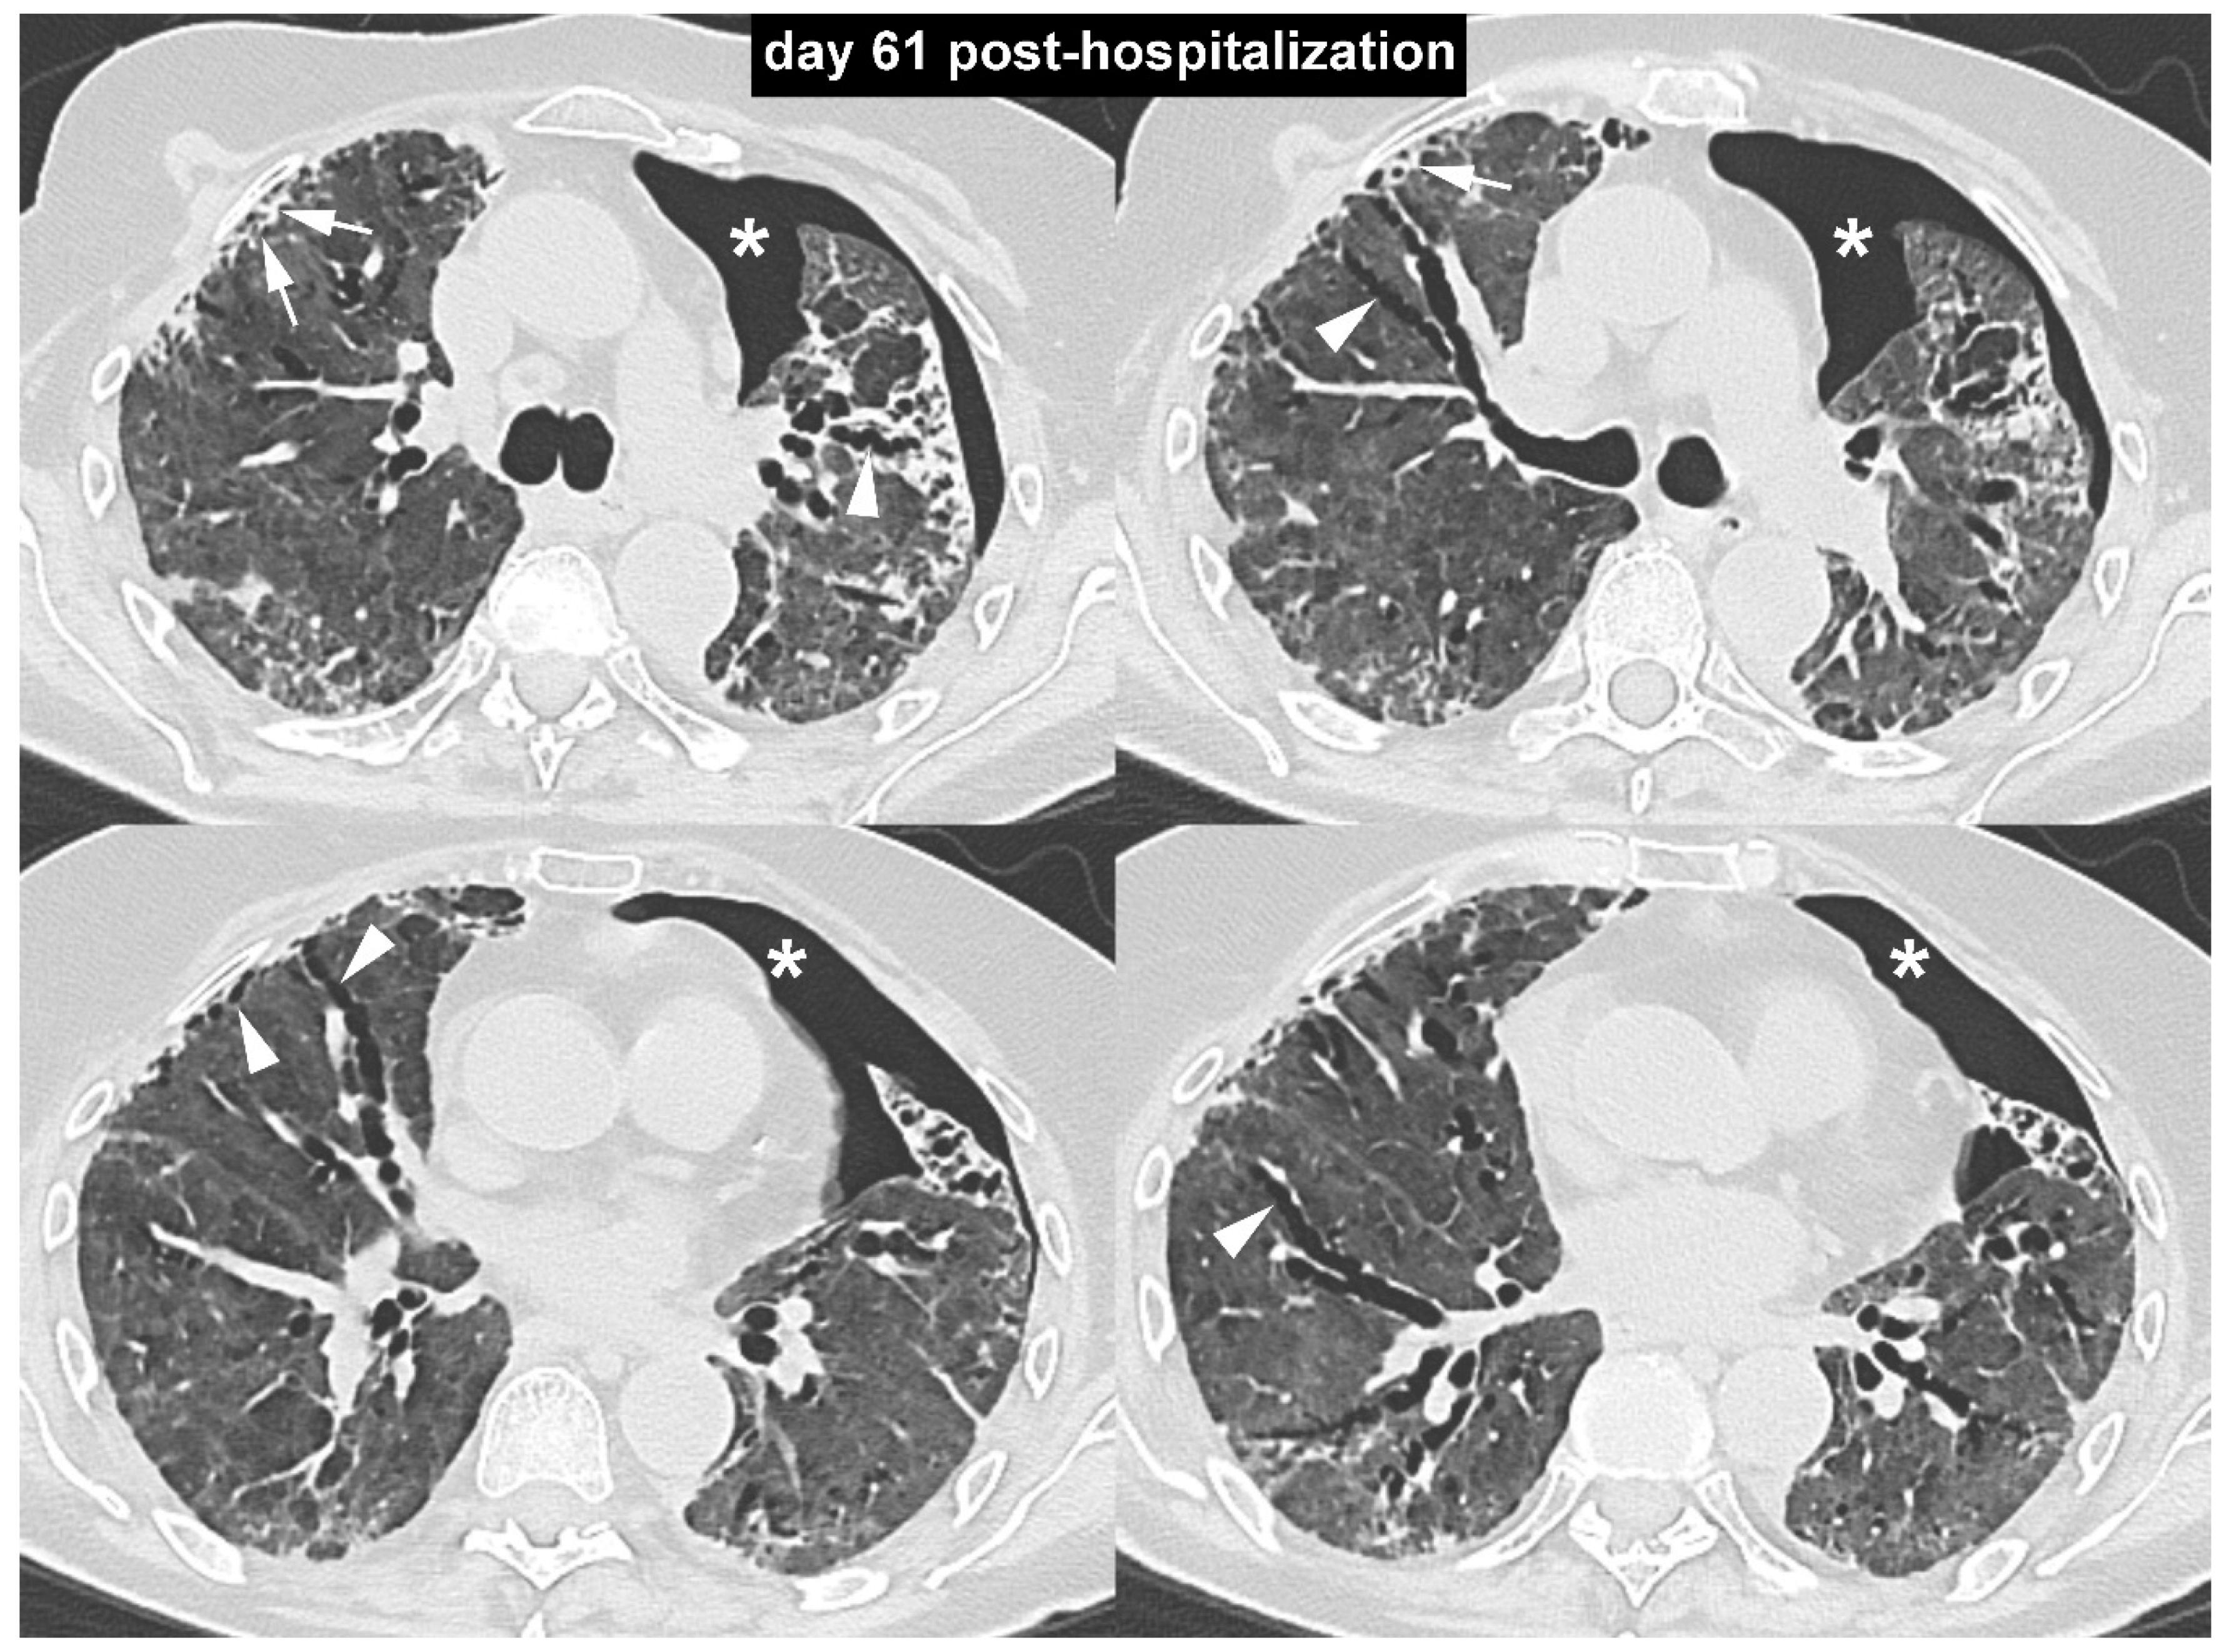

COVID-19 Pneumonia: Three Thoracic Complications in the Same Patient

Borghesi, A.; Aggiusti, C.; Farina, D.; Maroldi, R.; Muiesan, M.L. COVID-19 Pneumonia: Three Thoracic Complications in the Same Patient. Diagnostics 2020, 10, 498. https://doi.org/10.3390/diagnostics10070498